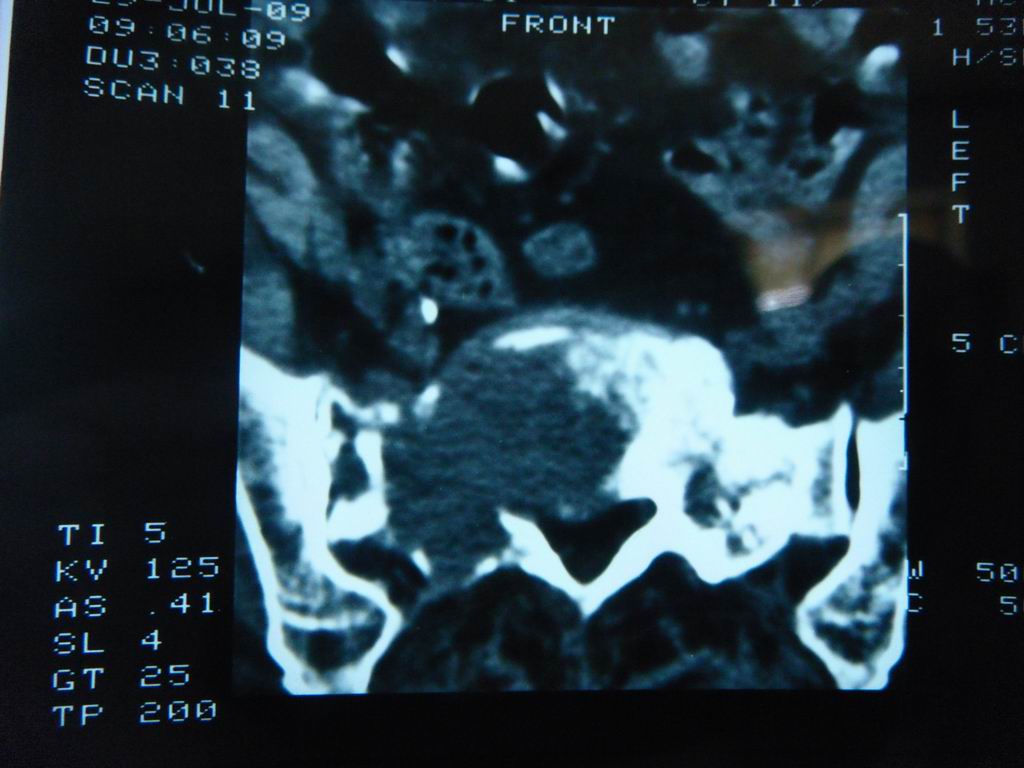

标题: CT21430:女性65岁 乳腺癌术后3年 [打印本页]

标题: CT21430:女性65岁 乳腺癌术后3年

结合病史,考虑骶骨转移瘤,但软组织肿块未突破骨壳,骨巨细胞瘤不能完全排除,骨髓瘤及脊索瘤不考虑。

结合病史,考虑骶骨转移瘤。

结合病史,考虑骶骨转移瘤。其它椎体,如腰5是否有问题呢?

个人感觉骨巨细胞瘤可能性大些。